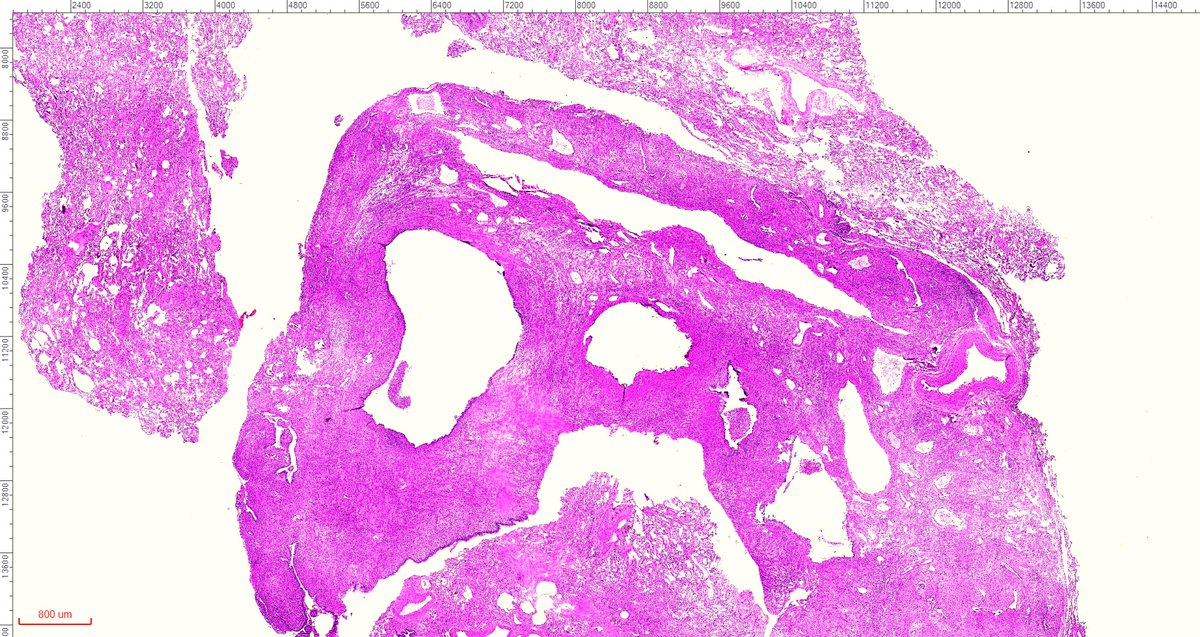

One of the most cryptic lesions for me in #pulmonarypath is the so called benign metastasizing leiomyoma. This case is a 37yo after myomectomy 3 years ago.

fabiotavora's tweet image. One of the most cryptic lesions for me in #pulmonarypath is the so called benign metastasizing leiomyoma. This case is a 37yo after myomectomy 3 years ago.